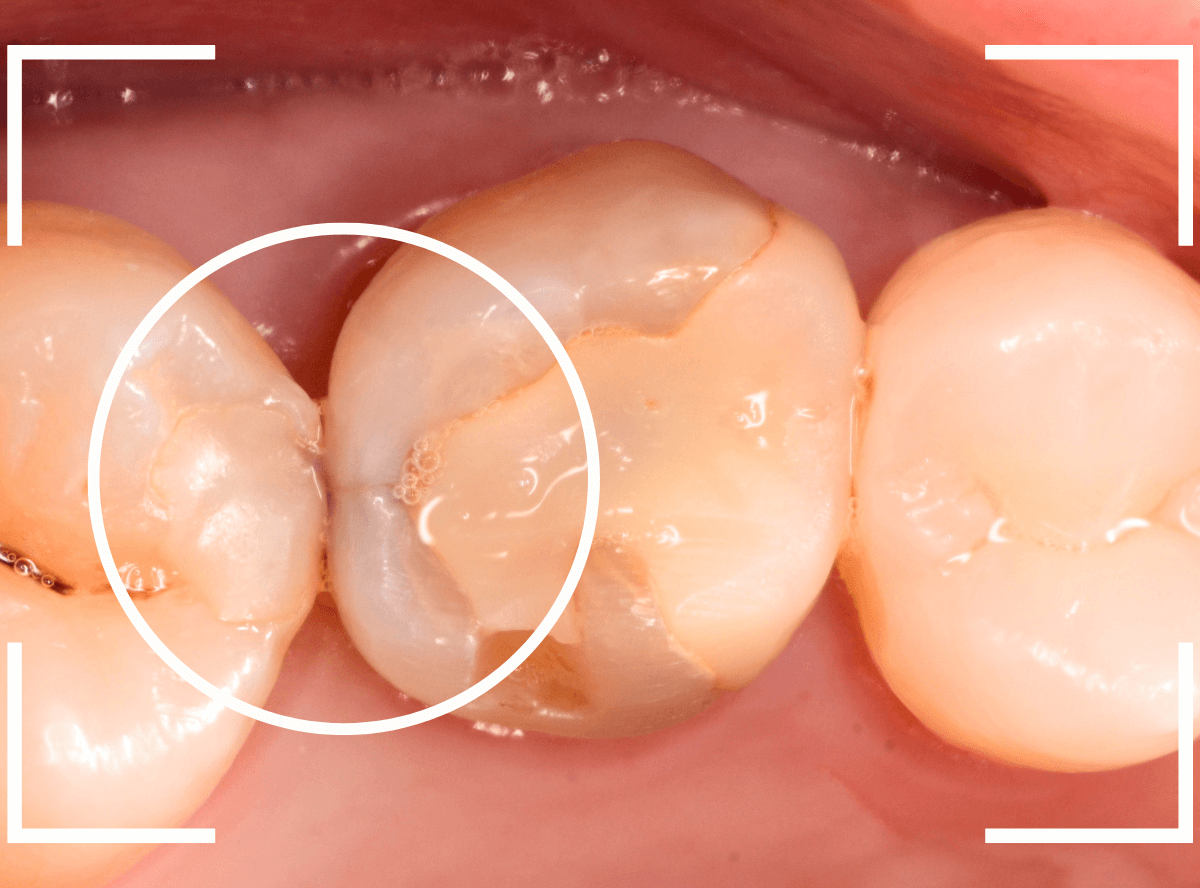

虫歯の治療を開始します。

隣の歯とのすき間を中心に広い虫歯になっていました。

虫歯治療後、特に症状もなく経過観察できましたので、つめものを作る治療に入ります。